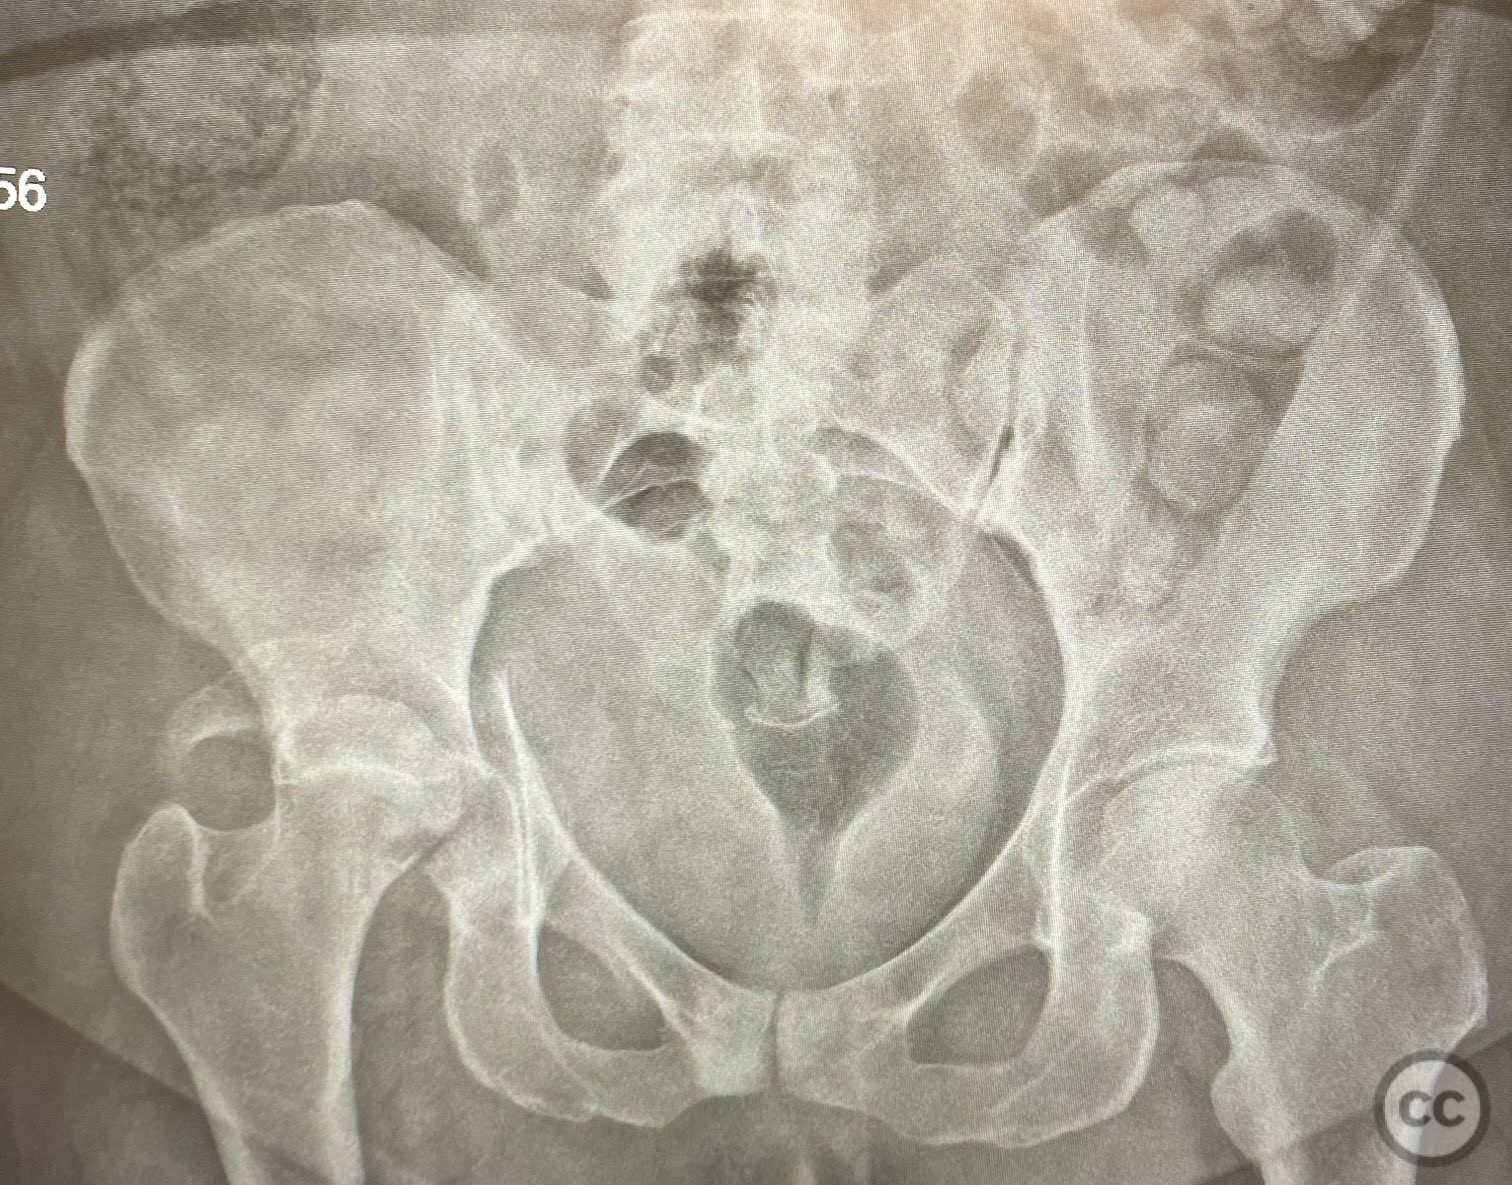

Clinical and radiological findings:  A high-speed motor vehicle collision resulted in a closed transverse acetabular fracture with associated comminuted posterior wall (PW) fracture-dislocation. The femoral head exhibited impaction and comminution, with local cancellous bone crushed and the femoral head itself also sustaining compressive injury from the denser acetabular bone. Neurovascular examination was unremarkable. Initial CT imaging delineated the acetabular fracture planes, displacement, comminution of the posterior wall, femoral head impaction, and absence of soft tissue attachment to the caudal PW fragment.